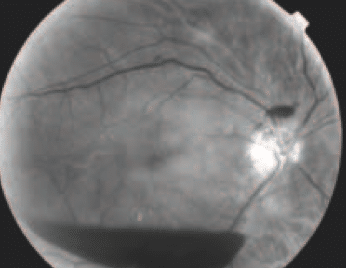

Différents aspects de cette vasodilatation irienne peuvent être notés : la collerette irienne (cercle artériel mineur de l’iris) n’est pas perfusée chez l’adulte ; la visualisation d’un courant sanguin dans cette collerette est donc un signe précoce de vasodilatation (indiquant en effet que la pression de perfusion de l’iris a augmenté) (fig. 1). D’autres signes évocateurs sont la visualisation anormale des vaisseaux radiaires et/ou une dilatation des capillaires du rebord pupillaire. Cependant, aucun de ces signes n’est une véritable néovascularisation ; ce ne sont que des signes d’alerte. La présence de ces signes dans l’œil atteint (alors que l’autre œil est normal) doit en effet faire redoubler de vigilance sur le risque de néovascularisation. Cette rubéose est d’aspect très différent, avec un aspect en chevelu formant plus ou moins une boucle complète (fig. 2). Il est de toute façon prudent, en présence de signes de vasodilatation isolée même sans rubéose, de pratiquer une gonioscopie soigneuse, car il arrive que la rubéose[...]